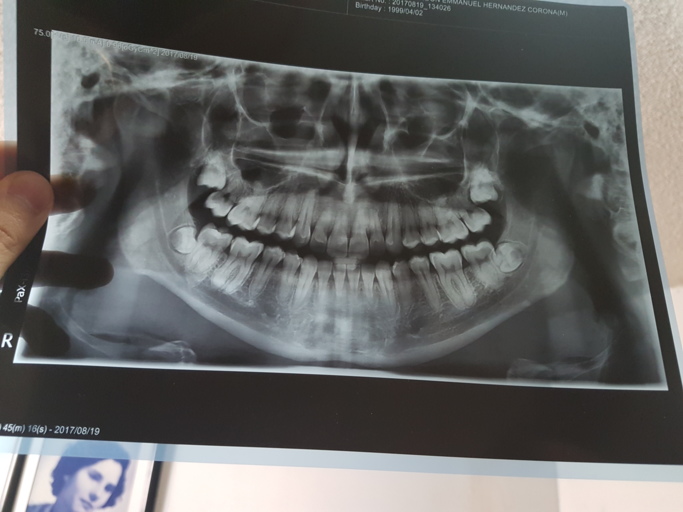

Hi, I'm Brandon, 19 year old. I am currently in this situation: I got removed dental braces for about 3 years ago. At that time, my dentist sent me to take a panoramic radiography just to check out if wisdoom teeth were correctly after braces. His conclusion was that he recommend me to extraxt the 4 wisdom teeth with a surgeon just to prevent any future complications. I didn't do anything at the time, just waited for any future pain or something, because i really didn't think the wisdom teeth extraction necesary. So I took another radiography a year ago (August 2017, in the image attached) just to check them with the surgeon. He told me the same old story, a recommendation to extract them, but this time, I GOT SCARED 'CAUSE the surgeon warned me that in the extraction it was little possibility to damage the down nerve of my mouth and also the sinus bone near the upper wisdom. I felt almost decided to extract them until that warning from the surgeon. So I recently got another surgeon opinion and it was totally the opposite, he told me he wouldn't care about nerve damage in extraction because all wisdom teeth were out of warning zones. Finally I got to mention that i have often aura migraines (1 or 2 per month) since a year. I found on the internet that ATM disfunction, wisdom teeth and other things can cause migraines, even false migraines with aura or something, but actually no surgeon or physician could relate both things (wisdom teeth and migraines). Actually I also have problems with hearing on my right side ear and my right side nose since 2 year or so, i mean i feel like clogged or congestioned like allergy.

Im not sure if the radiograph you uploaded is the most current, however if those were my teeth, I would schedule my extractions soon. If the teeth fully develop there is a much higher chance of nerve damage and perforation of the sinus. It is also an easier procedure to remove the teeth when the roots are still fused. When a dentist or surgeon recommends treatment, it is best not to wait for pain or further complications. If you have a small cavity, will you wait for it to abscess before getting it treated? Your wisdom teeth are never going to fully erupt on their own and can only create hygiene issues within your mouth. Some people are fortunate and have the space, however they too have issues keeping the areas clean and plaque free. The teeth are non-functioning in your case and it is best to seek treatment with an oral surgeon rather than continue to wait at this point.